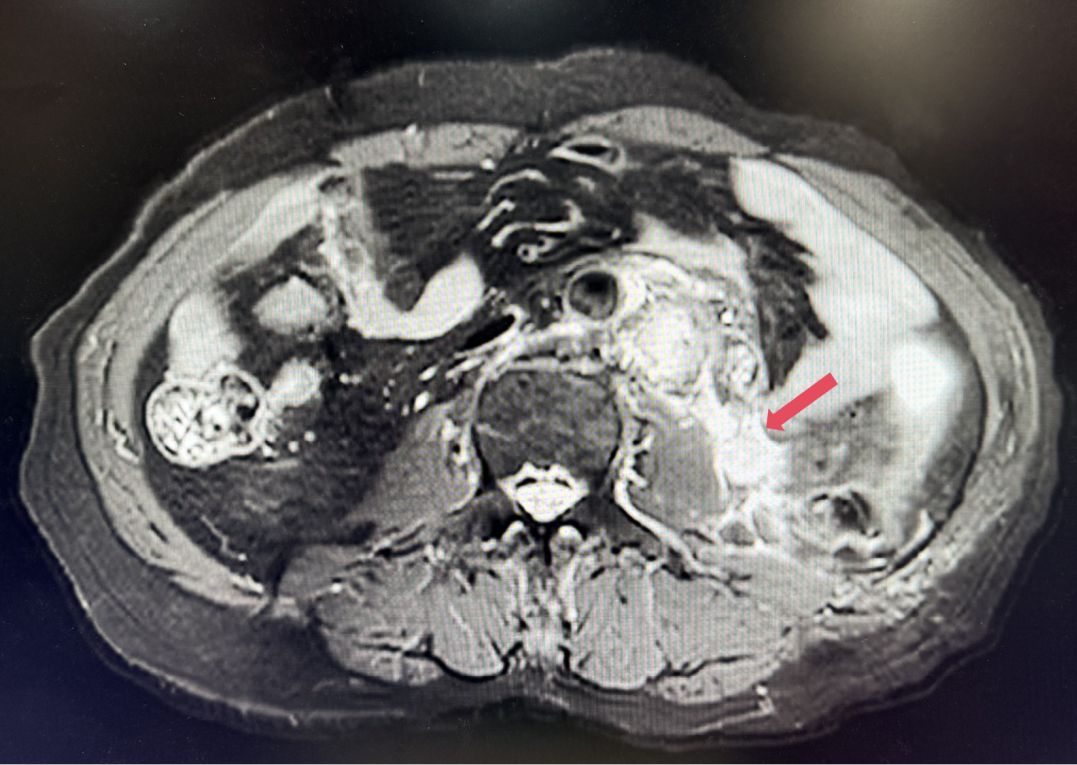

2023年11月,最深应答

2023年11月:治疗10个月(C15)评估,肿瘤负荷减少至41mm,维持PR。